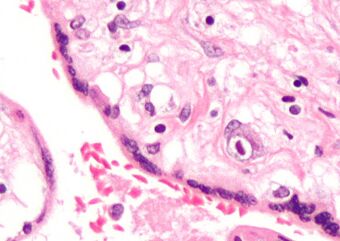

Micrograph of cytomegalovirus (CMV) infection of the placenta (CMV placentitis), a vertically transmitted infection: The characteristic large nucleus of a CMV-infected cell is seen off-centre at the bottom right of the image, H&E stain.

Apart from infecting the fetus, transplacental pathogens may cause placentitis (inflammation of the placenta) and/or chorioamnionitis (inflammation of the fetal membranes).[citation needed]

CMV placentitis